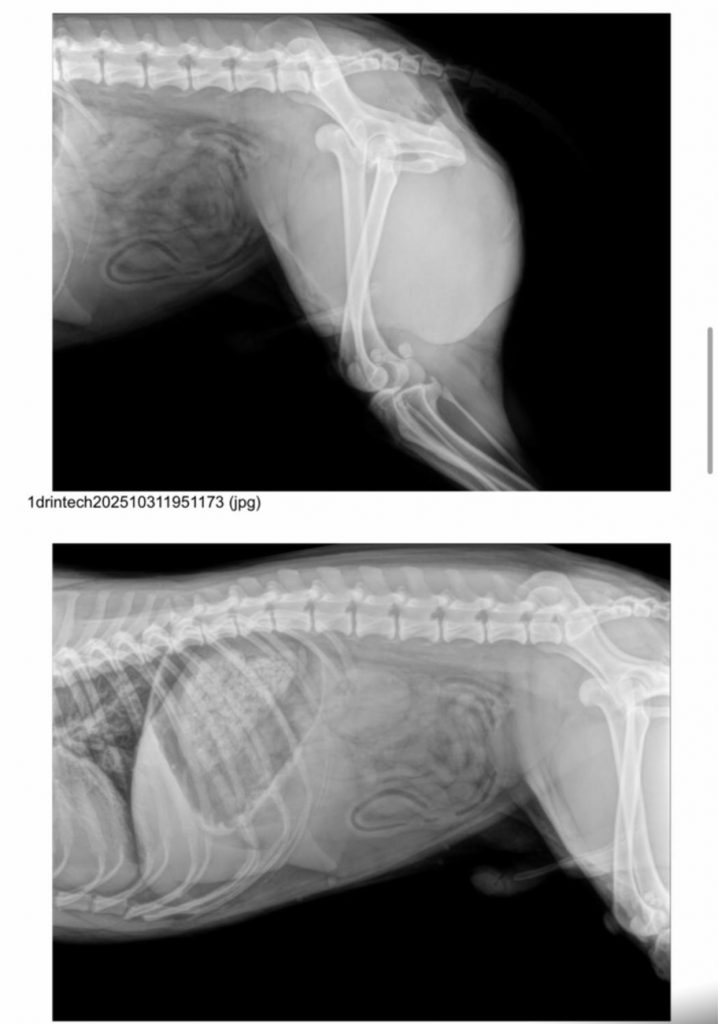

Born: 2024 – Breed: Podenco mix – Male

weighs 19 kilos.

He’s a good boy who recently came to live with us after being hit by a car, which dislocated his hip. He’s currently recovering well from surgery. Son is very easy to handle and lets us treat him; he even licks your hands while you do it. He’s a trusting dog who readily accepts your requests. He walks well on a leash and is very attentive to anything you ask of him. He gets along well with other dogs, both male and female, large and small, and we’re sure he’ll start playing with them soon. Although he’s a young Podenco, he has a very calm energy and has rested without any problems after surgery. We believe he’s a good boy who deserves a family to play and go for walks with. Despite his hip injury, he can live a normal life, going on hikes and doing anything his new family wants him to do.